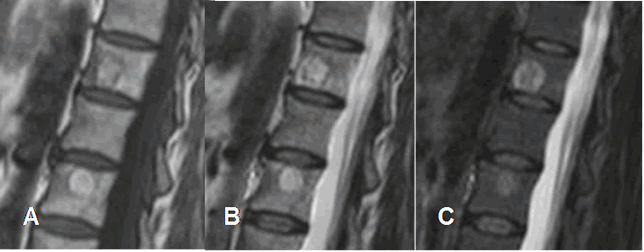

Fig 153. Hemangiomas múltiples.

A: RM sagital en T1, B: RM sagital en T2 y C: RM sagital en STIR. Múltiples hemangiomas vertebrales y en el sacro, que suprimen en el STIR.

Fig 154. Hemangiomas sintomáticos.

A: RM sagital en T1, B: RM sagital en T2 y C: RM sagital en STIR. Hemangiomas vertebrales hiperintensos en T1 y T2, que no suprimen en STIR, por componente inflamatorio asociado.